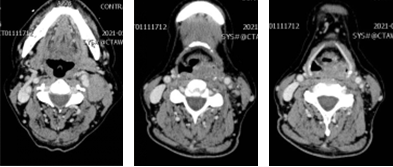

现病史:患者6月前无明显诱因出现左侧颈部肿物,直径约6cm,无咽喉不适,我院门诊电子喉镜示“左侧下咽新生物”。纤维喉镜下活检示低分化鳞癌。患者接受TPF化疗方案3个疗程,下咽部及颈部肿物无明显改变。

电子喉镜显示:左侧梨状窝内侧壁肿物,累计梨状窝尖。

图片